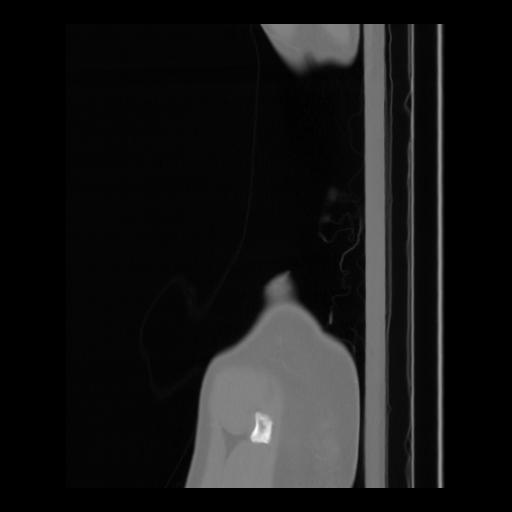

36 CUERPO,CE,Sagittal,3.000,CUERPO,Sagittal,